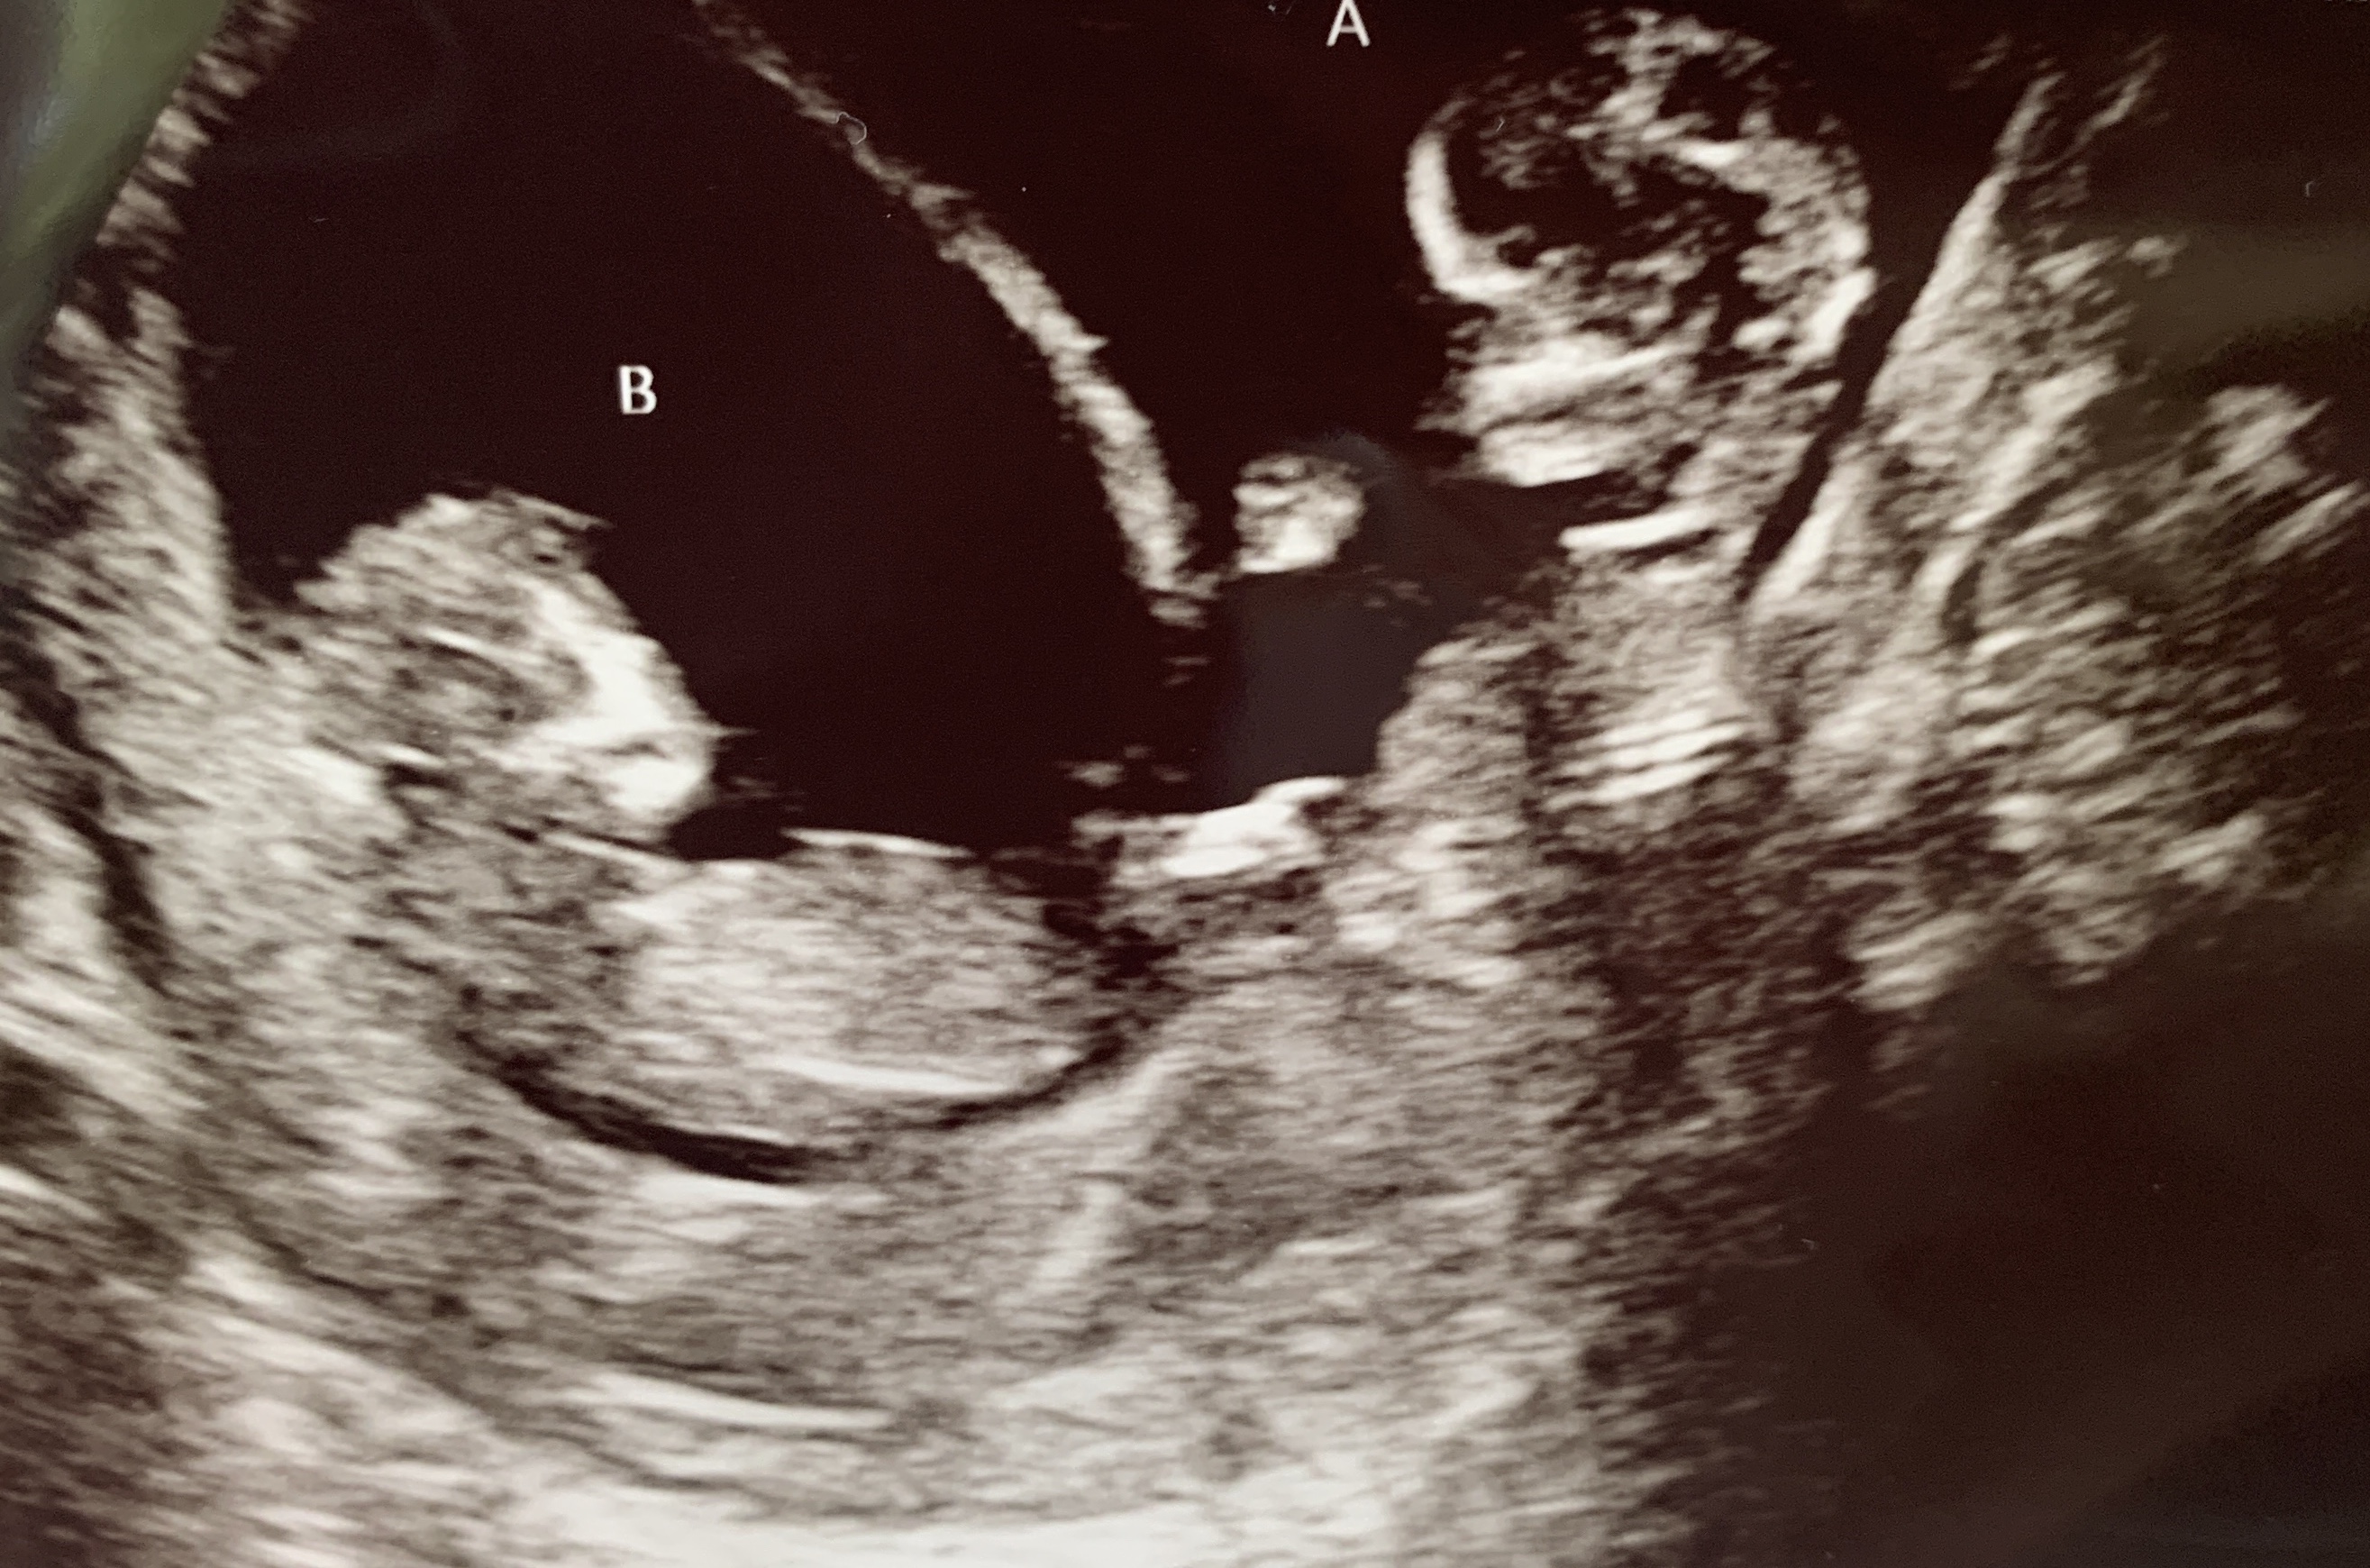

This is a twin transvaginal ultrasound at 7w3d